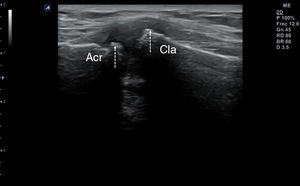

Ecografía clínica en la artrosisTécnica de exploraciónLa evaluación ecográfica de la artrosis depende de la localización de la articulación que se pretenda analizar. De todas ellas, la más estudiada es la rodilla. Para explorarla, se realizan cortes transversales con la rodilla en flexión forzada, en los que se podría observar una disminución del grosor del cartílago hialino (grosor normal en torno a 2mm) y calcificaciones puntiformes o lineales paralelas a la cortical ósea (fig. 6), lo que se ha dado en llamar «patrón punteado» o «en bandas de rosario»10. También cabría explorar mediante cortes longitudinales las caras medial y lateral en los que se pueden visualizar irregularidades en la cortical ósea que corresponderían a osteofitos (fig. 7), así como en el receso suprapatelar con la rodilla en semiflexión de 20-30° hallar distintos grados de sinovitis (fig. 8). Datos como la sinovitis, tradicionalmente estudiada en pacientes con artritis reumatoide procedentes de estudios basados no solo en ecografía sino también en otras pruebas radiológicas como la resonancia magnética (RM), están modificando el conocimiento que tenemos sobre la patogénesis de la artrosis que se había considerado clásicamente una enfermedad no inflamatoria; dejando ver un modelo más complejo con implicación de todas las estructuras articulares11–13.

Por último, respecto de otras articulaciones como la cadera, se encuentran muy escasos estudios centrados en la artrosis como patología. Sí aparecen estudios centrados en el empleo del ultrasonido como ayuda para técnicas ecoguiadas que ocupará otro epígrafe del presente artículo. En los pocos artículos disponibles no se define la exploración de forma sistematizada salvo en alguno de ellos, que recomienda utilizar un corte paralelo al cuello femoral con la cadera en ligera rotación externa y la rodilla en flexión de 30°. De esta manera, en las imágenes se pueden observar osteofitos como irregularidades de la cortical ósea, o anormalidades de la cabeza femoral como aplanamiento o pérdida del contorno15 (fig. 9).